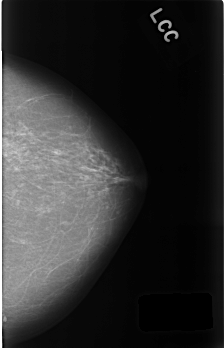

C_0454_1.RIGHT_CC

FILE: C_0454_1.RIGHT_CC.OVERLAY

TOTAL_ABNORMALITIES 1

ABNORMALITY 1

LESION_TYPE MASS SHAPE LOBULATED MARGINS CIRCUMSCRIBED

ASSESSMENT 3

SUBTLETY 5

PATHOLOGY BENIGN_WITHOUT_CALLBACK

TOTAL_OUTLINES 1

BOUNDARY